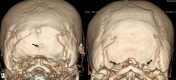

Objective The posterior condylar canals (PCCs), posterior condylar veins (PCVs), occipital foramen (OF), and occipital emissary vein (OEV) are potential anatomical landmarks for surgical approaches through the lateral foramen magnum. We performed the study to make morphometric and radiological analyses of the various emissary foramens and vein in the posterior cranial fossa. Methods Morphometric study were performed on 95 dry occipital bones and radiological analyses on computed tomography (CT) angiography images of 150 patients. The number of OFs on both sides was recorded and PCC length and mean diameters of the internal and external orifices of PCC were measured for bony specimens. Prevalence of PCV and PCV size was investigated using CT angiography. Results Mean PCC length was higher in the left side (9.85 ± 2.5). Mean diameter of the internal orifice and the external orifice diameter were almost the same. The majority of PCCs (75-79.33%) had 2 to 5 mm diameter; only 4 to 9.2% were small in size (< 2 mm). In CT angiography, PCV was not identified in 23 (15.33%) patients. PCVs were located bilaterally in 105 (70%) and unilaterally in 22 (20.5%) patients. Only 11.3% of PCVs were large in size (> 5 mm), 80% of PCVs were medium sized (2-5 mm), and 8.6% were small sized (< 2 mm). Conclusion Normal values of OF, PCC, PCV, and OEV could serve as a future reference for the understanding of the physiology of craniocervical venous drainage, which is necessary to avoid surgical complications and can also serve as a guide to surgical interventions for pathologies of the posterior cranial fossa, such as tumors and injuries.